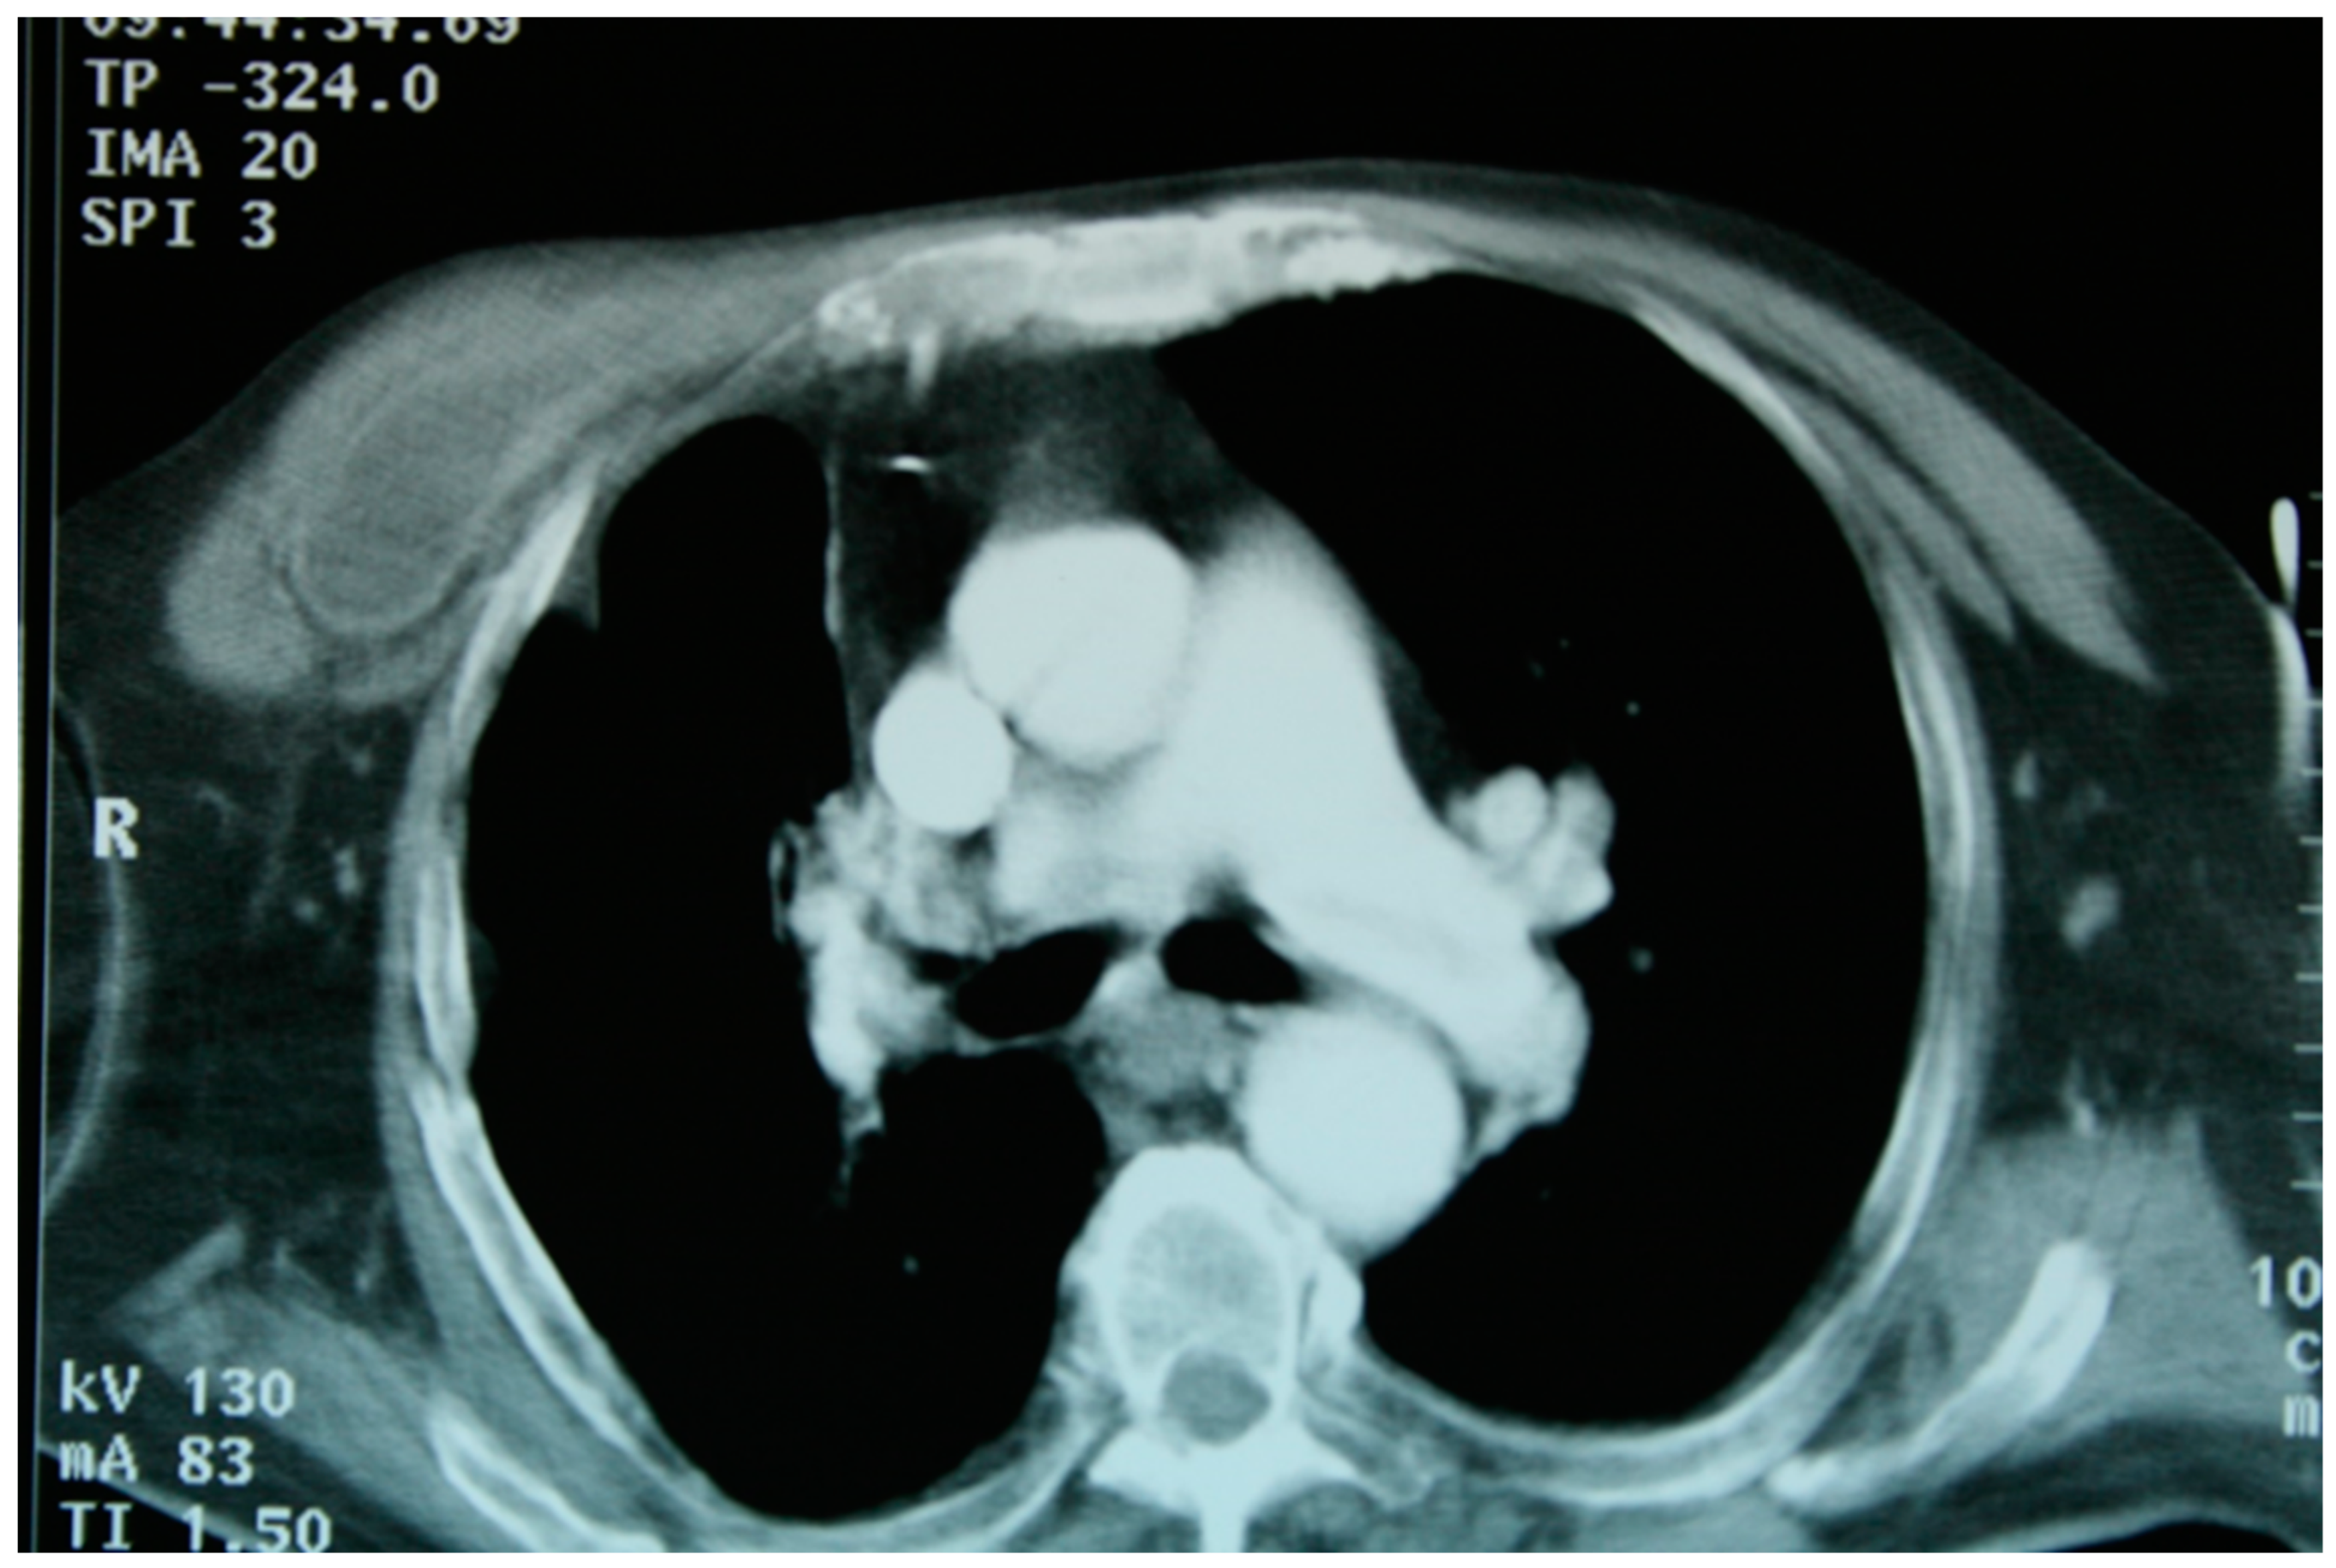

A patient with multiple bilateral lung lesions was diagnosed after investigations for a large hepatic lesion that turned out to be echinococcosis. A 41-year-old male patient reported abdominal pain and shortness of breath and was referred to the hospital by a primary care physician. Primary radiological investigations revealed a large hepatic lesion and multiple bilateral pulmonary lesions. Magnetic resonance imaging (MRI) was performed to evaluate the hepatic lesion (Figure 1), while chest X-rays and computed tomography (CT) were performed prior to admission to the Department of Thoracic Surgery. CT detected two right lower lobe lesions in segment 6 (diameters 4.6 cm, 1.4 cm) and one in segment 8 measuring 1 cm. In the left lower lobe, there was a single 4 cm lesion in segment 9 (Figure 2).

Figure 1. (A,B): T2-weighted hyperintense liver lesion; (C): T1-weighted hypointense liver lesion with abnormal pulmonary lesions.